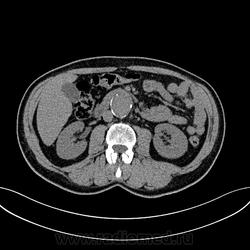

Пациент лежит в кардиологии. Прислали на аортографию. 2 врача УЗИ несколько разошлись в диагнозах: одна видит тромбированную аневризму брюшной аорты, другая - тромбоз нижней полой вены.

А мы получили вот такие красивые картинки.

Шикарно! Тромбированная аневризма инфраренального отдела (над бифуркацией), бифуркации и общих подвздошных артерий, синдром Лериша справа.

И еще маленькая аневризмочка наружной подвздошной слева. Честно говоря, меня больше всего впечатлили коллатерали, благодаря которым клинически он вообще не соответствует исследованию. Конечности теплые, пульсация слабая, но как-то прослеживается...